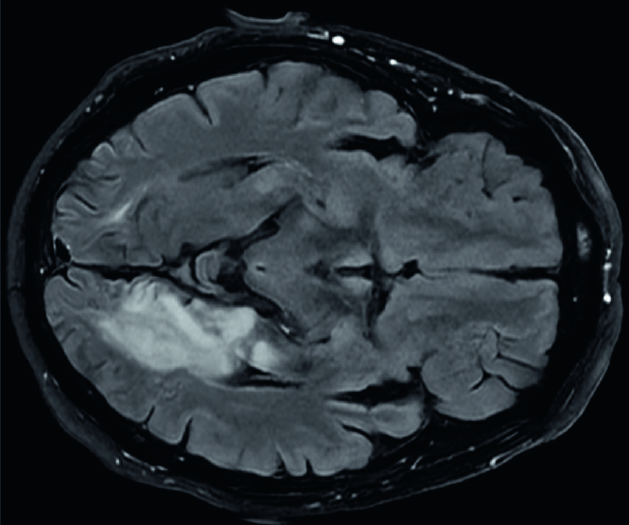

Alexi utan agrafi – att inte kunna läsa vad man själv har skrivit

Fallbeskrivning

Ovanligt och svårupptäckt strokesyndrom.